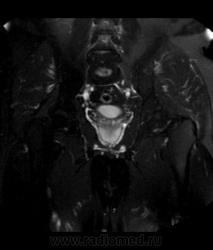

Для динамического контрастирования требуется инъектор, у нас с ним технические неполадки, поэтому контрастное вещество вводим от руки. Но в данном случае четко видно проростание опухолевого компонента через мышечный слой мочевого пузыря, даже некоторой инфильтрацией паравезикальной клетчатки. По гистологии плоско-клеточный рак. У пациента множественные метастазы в легких.